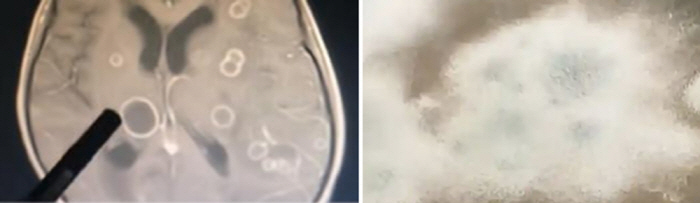

[스포츠조선 장종호 기자 6세 중국 소녀의 뇌에서 수십 개의 '구멍'이 발견돼 충격을 주고 있다.

의료진은 구멍 안의 고름을 채취해 검사를 진행했고, 그 결과 곰팡이(진균)의 일종인 '아스페르길루스 푸미가투스(Aspergillus fumigatus)'에 감염된 것이 확인됐다.